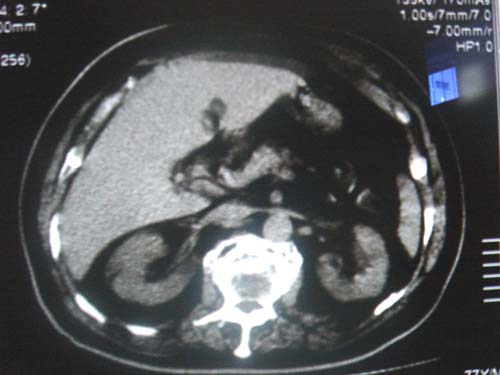

请大家看一下,肝左叶前缘低密度影考虑什么?只有这一层。

少量腹水? 包膜下脂肪?建议mr定性。

肝脏左叶不象病变。

包膜下正常组织,并非积液.

测ct值,可能是伪影,脂肪组织,积液

我个人认为本片正常,可能是容积效应引起的.

我认为本片正常,可能是容积效应引起的.

经各位老师一说,我还真拿不准了,最好连续层面观察就能鉴别是否是膈肌及容积效应所致。细节决定成败,期待高手帮忙解惑!!!不过本人还是支持正常表现的。